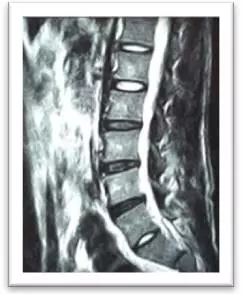

(術(shù)中)

4月8日,在局麻下,劉志安副院長親自實施了腰5/骶1椎間盤突出癥經(jīng)脊柱內(nèi)鏡髓核摘除術(shù),術(shù)中摘除了大塊脫出髓核組織。